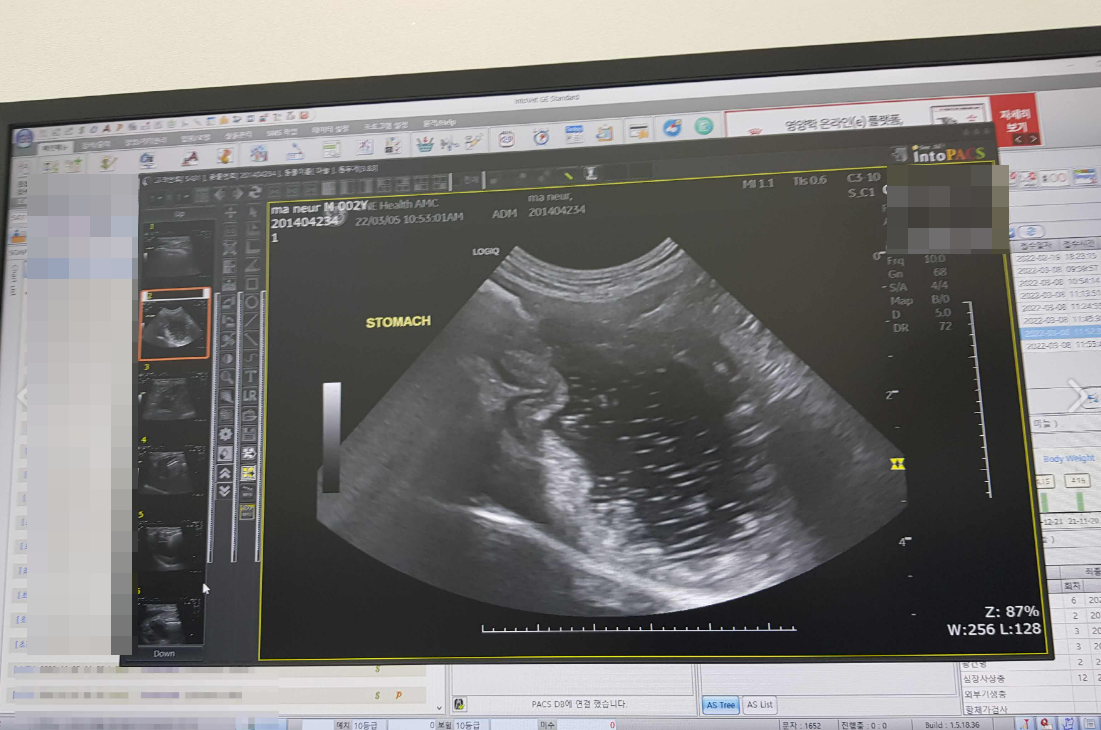

강아지 심장사상충은 세균균사에 의해 발생하는 강아지의 질병으로, 모기에 의해 전염된다. 모기가 감염된 개의 혈액을 빨아들이면 세균균사의 알이 모기의 입자에 존재하게 된다. 그 후 모기가 강아지의 피부를 물면 세균균사의 알은 강아지의 혈관으로 들어가게 된다.

강아지 심장사상충은 이름처럼 심장에서 발생하는 것이 특징으로 감염된 강아지의 심장에서 세균균사가 성장하고 번식하면서 심장 및 폐동맥을 막아서 심장 및 폐 기능이 저하될 수 있으며 심할 경우에는 사망에 이르기도 한다.